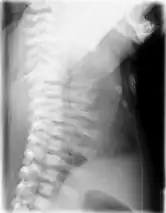

Lateral CXR of the same person above

Jeune syndrome is a rare genetic disorder that affects the way a child's cartilage and bones develop. It begins before the child is born and primarily affects the child's rib cage, pelvis, arms and legs.[5] Usually, problems with the rib cage cause the most serious health problems for children with Jeune syndrome. Their rib cages (thorax) are smaller and narrower than usual, which inhibits the child's lungs from developing fully or expanding when they inhale. The child may breathe rapidly and shallowly. They may have trouble breathing when they have an upper or lower respiratory infection, like pneumonia. Breathing trouble can range from mild to severe. In some children, it is not noticeable, aside from fast breathing; however, in others, breathing problems can be fatal. About 60% to 70% of children with this condition die from respiratory failure as babies or young children. Children with Jeune syndrome who survive often develop problems with their kidneys, and over time they may experience kidney failure.[2] As a result, few children with Jeune syndrome live into their teen years. Children with Jeune syndrome have a form of dwarfism. They are short in stature, and their arms and legs are shorter than most people's.[6]